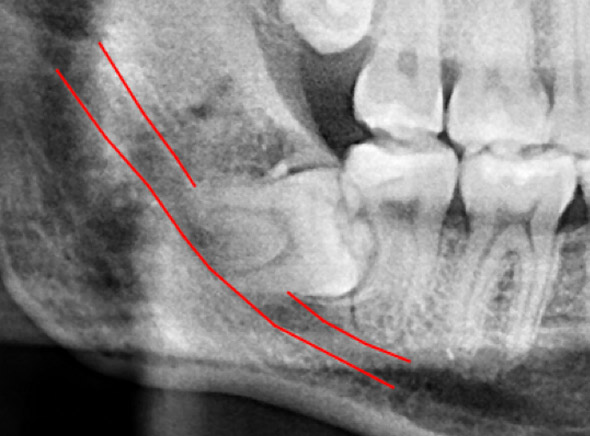

(兩條紅線中間黑色區域即為神經管)